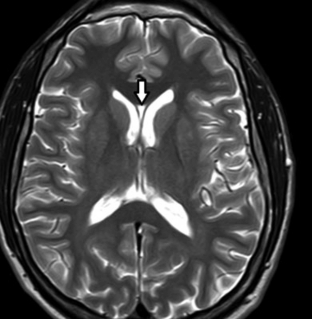

Constituyen variantes anatómicas que se presentan en la línea media derivando de alteraciones del desarrollo del septum pellucidum (SP).7 En TC y RM se los aprecia con densidad o señal similar al LCR (►Figs. 1, 2, 3).7

Resonancia magnética (RM) de cerebro, corte axial ponderado en T2: la flecha señala al cavum septum pellucidum (CSP) entre las astas frontales de los ventrículos laterales.